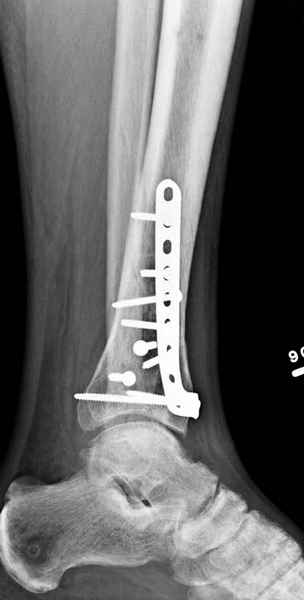

Публикации за последние пять лет показывают, что в лечении переломов

пилона важным является состояние мягких тканей. Поэтому при лечении

пилона, особенно после высокоэнергетической травмы, необходимо

придерживаться правила - лучше проводить запоздалую фиксацию, чем после

операции иметь проблемы с мягкотканными осложнениями.

Закрытый метод фиксации рекомендуется, когда фрагменты были сопоставлены

в результате лигаментотаксиса, а открытый минимальный метод при

нерепонированных отломках.

После репозиции сустава необходимо удостовериться

в заполнении образовавшейся полости ауто- или синтетическими

заполнителями, что в последующем предохраняет от варусного коллапса.

Фиксация наружной лодыжки подсказывается переломом, а малоберцовая

является ключом-ориентиром для длины конечности.

Любая фиксация - преконтурированные пластины с уголовой стабильностью,

медиальная, латеральная в зависимости от нахождения отломков или

наружная фиксация типа аппарата Илизарова подходят для ранней мобилизации.

Не все переломы пилона фиксируются медиальной

пластиной,  поэтому, учитывая что большой фрагмент

находится на латеральной стороне, я бы применил

передне-латеральную пластину.